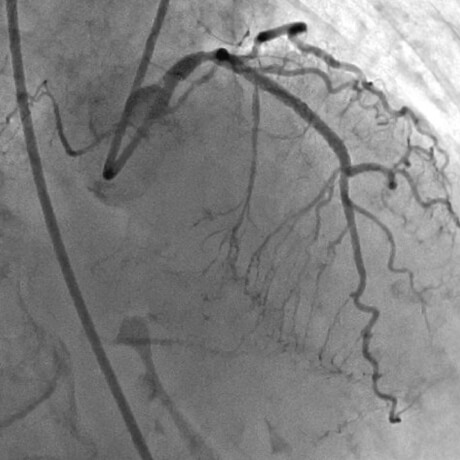

急性心筋梗塞症例へのPCI施行時の冠動脈造影画像

冠動脈が完全閉塞した急性心筋梗塞